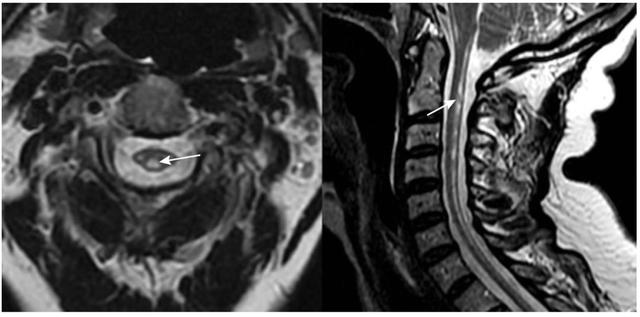

2. 结构性病变

原发性脑肿瘤,如脑膜瘤和胶质瘤,以及继发于黑色素瘤、乳腺癌和肺癌的转移性肿瘤,可出现急性共济失调(图5)。同样,其他儿童后颅窝脑肿瘤,包括小脑星形细胞瘤和髓母细胞瘤,也可能伴有ACA和第四脑室出口梗阻的脑积水。其他占位性病变也出现,如小脑病变、脓肿、动静脉畸形等。

表格总结+实战读片:掌握急性小脑性共济失调的常见病因及诊断线索丨临床必备

图5 表现为急性共济失调的肾移植患者。增强MRI可见小脑环形强化病灶;活检证实为中枢神经系统移植后淋巴组织增生性疾病。